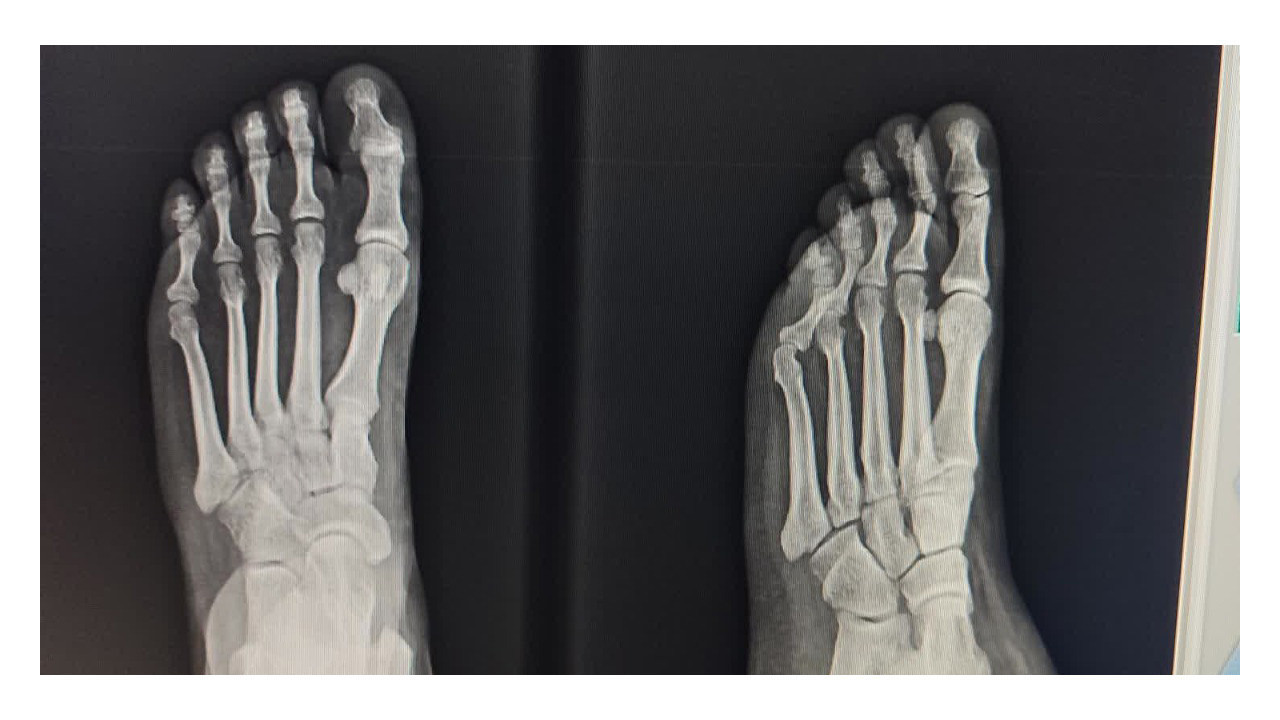

Kocaeli’de bir vatandaşın Şikayet Var adlı internet sitesinde yaptığı paylaşım, “Acil serviste kim acil?” sorusunu yeniden gündeme taşıdı. Körfez Devlet Hastanesi Acil Servisi’nde yaşandığı iddia edilen olay, sosyal medyada ve kamuoyunda tartışma yarattı. Şikayet Var platformunda yer alan paylaşıma göre olay, 13 Aralık 2025 Cumartesi gecesi saat 22.30 sıralarında Kocaeli Körfez Devlet Hastanesi Acil Servisi Triaj bölümünde yaşandı. Vatandaş, eşinin ayağında ya da ayak bileğinde çatlak olabileceği şüphesiyle hastaneye başvurduklarını ve acil olarak röntgen çekilmesi gerektiğini belirttiğini ifade etti.

13.12.2025 tarihinde saat 22.30 sularında, eşimde kırık ya da çatlak olabileceği şüphesiyle Kocaeli Körfez Devlet Hastanesi Acil Servis Triaj Bölümüne başvurdum. Acil olarak röntgen çekilmesi gerektiğini belirtmeme rağmen, triajda bulunan bir erkek ve bir kadın personelin ilgisiz ve laubali tavırlarıyla karşılaştım. Durumu defalarca anlatmama rağmen, yalnızca yeşil alana yönlendirilmekle yetindiler ve sürece dair hiçbir şekilde yardımcı olmadılar.